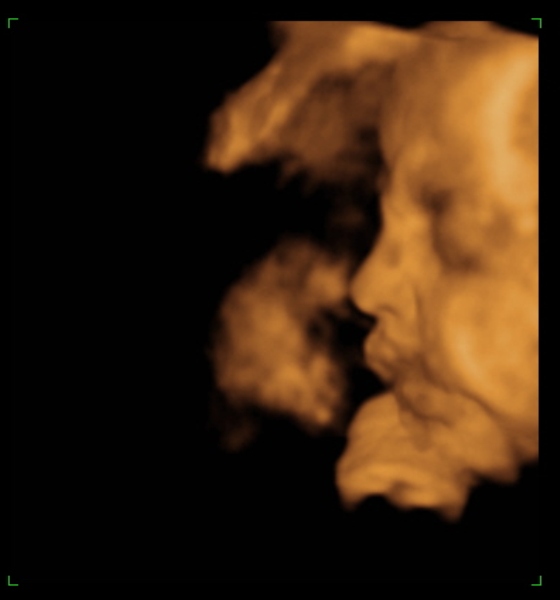

Tegnap megjártuk a 4D-t, nagyon szép husis a kisasszony :lol: persze aludt, nem kommunikált velünk, akármit ettem, ittam, csináltam. :lol: De azért féloldalasan aludt, úgyhogy csak láthattuk, volt mosoly, ásítás, fintor :lol: :lol:

Ja, és itt is megállapították, hogy nagy a talpa :lol: :lol: :lol: És a fejecskéje is, úgyhogy azt mondták majd megdolgoztat szülésnél, gondoltam "tök jó" :lol: :roll:

Ja, és a képek lemaradtak :D

Kép mosolygom:)

Kép ásítok, UFO nyitott szemeimmel:))))

Kép profilból

Kép nagy tapppppancsom:)

Persze a kis keze mindenhol ott van :lol: Bocsi, ha picit sok voltam :oops: 8)